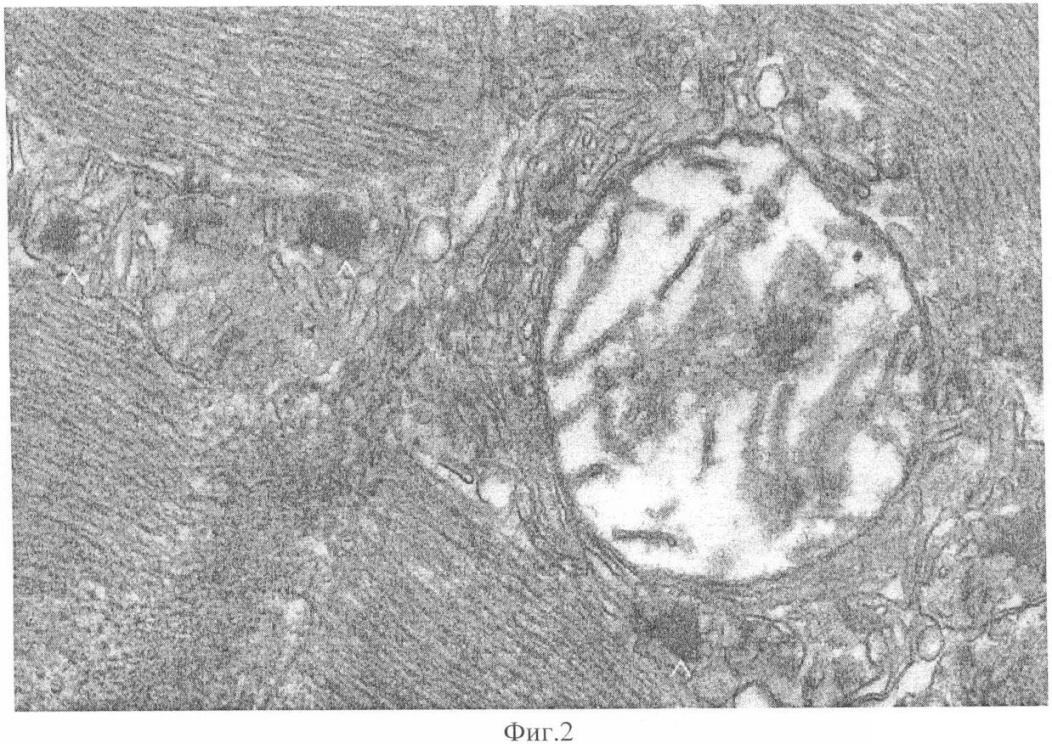

Энтеровирусы определяли количественно в зоне разрыва миокарда и вне зоны инфаркта методом модифицированной реакции связывания комплемента (м-РСК). Вирусы герпеса выявляли методом ПЦР. Вирусологический контроль исследований проводили при помощи электронной микроскопии (Фиг.1, 2). Титры энтеровирусов по исследованным зонам представлены в таблице 1.